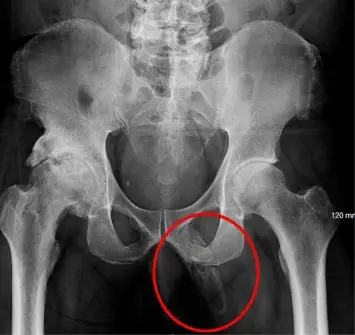

As per the Urology Case Report, the man's 'physical exam was negative except for a penile pain', sparking him to undergo an x-ray 'to rule out any fracture showed a severe, asymmetric degenerative changes of the right hip'.

The patient went on to be diagnosed with penile ossification - an extremely rare condition with fewer than 40 cases reported.

Penile ossification occurs when calcium salts build up in the soft tissue of the penis, forming extraskeletal bone.

"It is not well understood what initiates the ossification. Probably fibrosis starts initially and this with continuous stimulation leads to proliferation and metaplasia. Diagnosis is confirmed on radiological and histopathological findings."